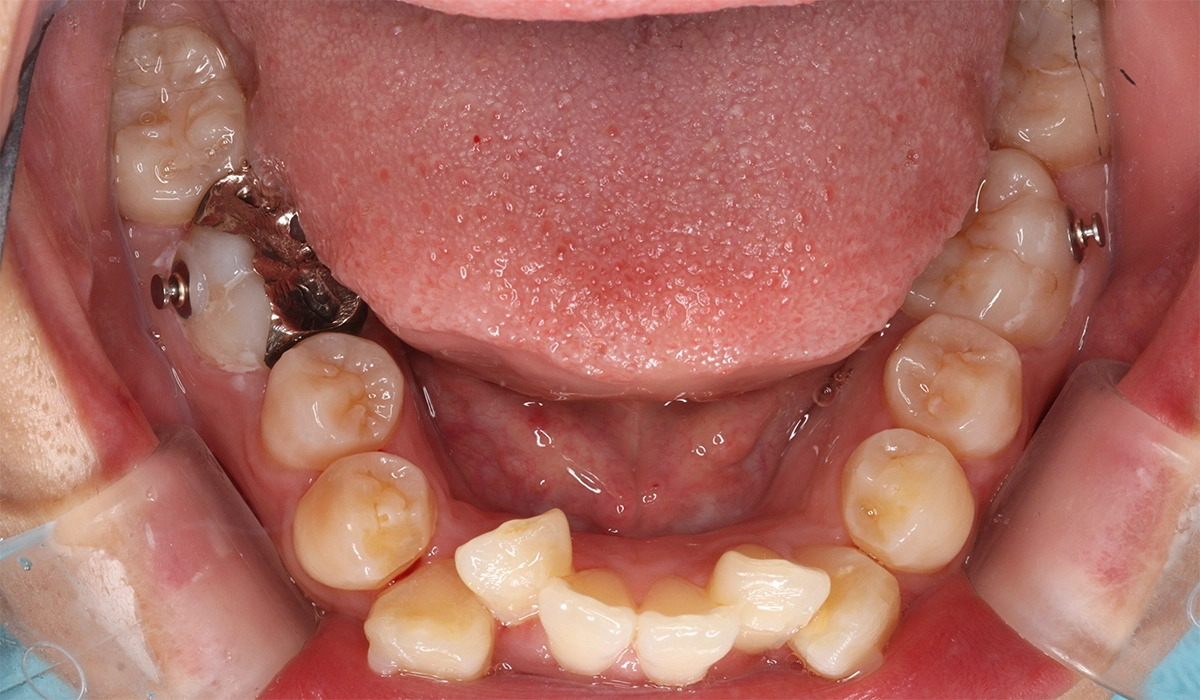

術前:下顎